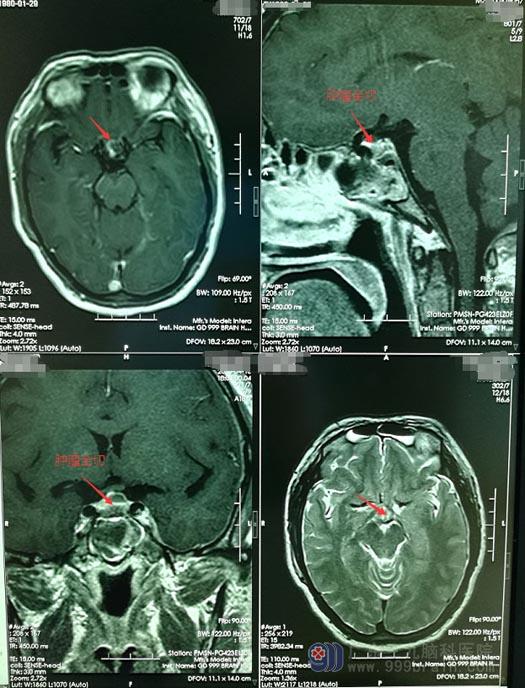

完善术前准备后,医院副院长、神经外五科主任鲁明带领治疗团队为小玲实施内镜下“经鼻蝶鞍区占位切除术”,手术非常顺利。

术后,小玲神志清楚,言语表达流利,视力视野未见异常,四肢活动自如,双眼视力改善,未出现尿崩;术后复查头颅CT显示:肿瘤全切。